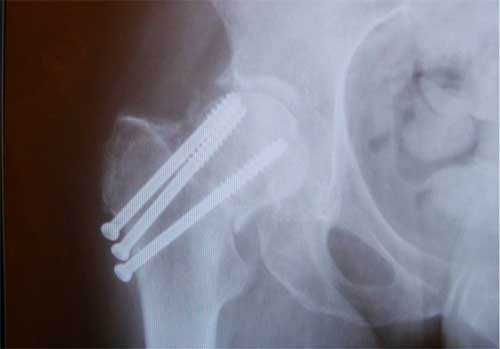

Остеосинтез ТБС на рентгене

Остеосинтез при переломе шейки

При ПШБ в основном проводится внутренний (погружной) остеосинтез. То есть, специальная фиксирующая конструкция соединяется непосредственно с костными структурами после оперативного обнажения места перелома. В ортопедии применяют два вида внутреннего соединения репонированных отломков:

- интрамедуллярный (внутрикостный);

- экстрамедуллярный (накостный).

Интрамедуллярный метод

При интрамедуллярной технике дистальный и проксимальный отломки соединяются специальными стержнями или штифтами, проведенными через костномозговой канал каждого из них. Сегодня преимущество на стороне эндосистем блокирующего типа. На их противоположных концах имеются уже готовые отверстия для винтов или своеобразные загибы, повышающие степень стабилизации системы. Интрамедуллярными устройствами, которые бывают ригидными или полуэластичными, возможно зафиксировать даже множественные осколки.